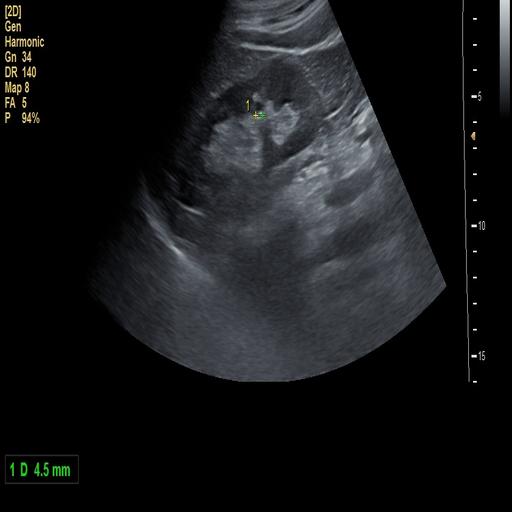

数据样例

结石肾脏样例